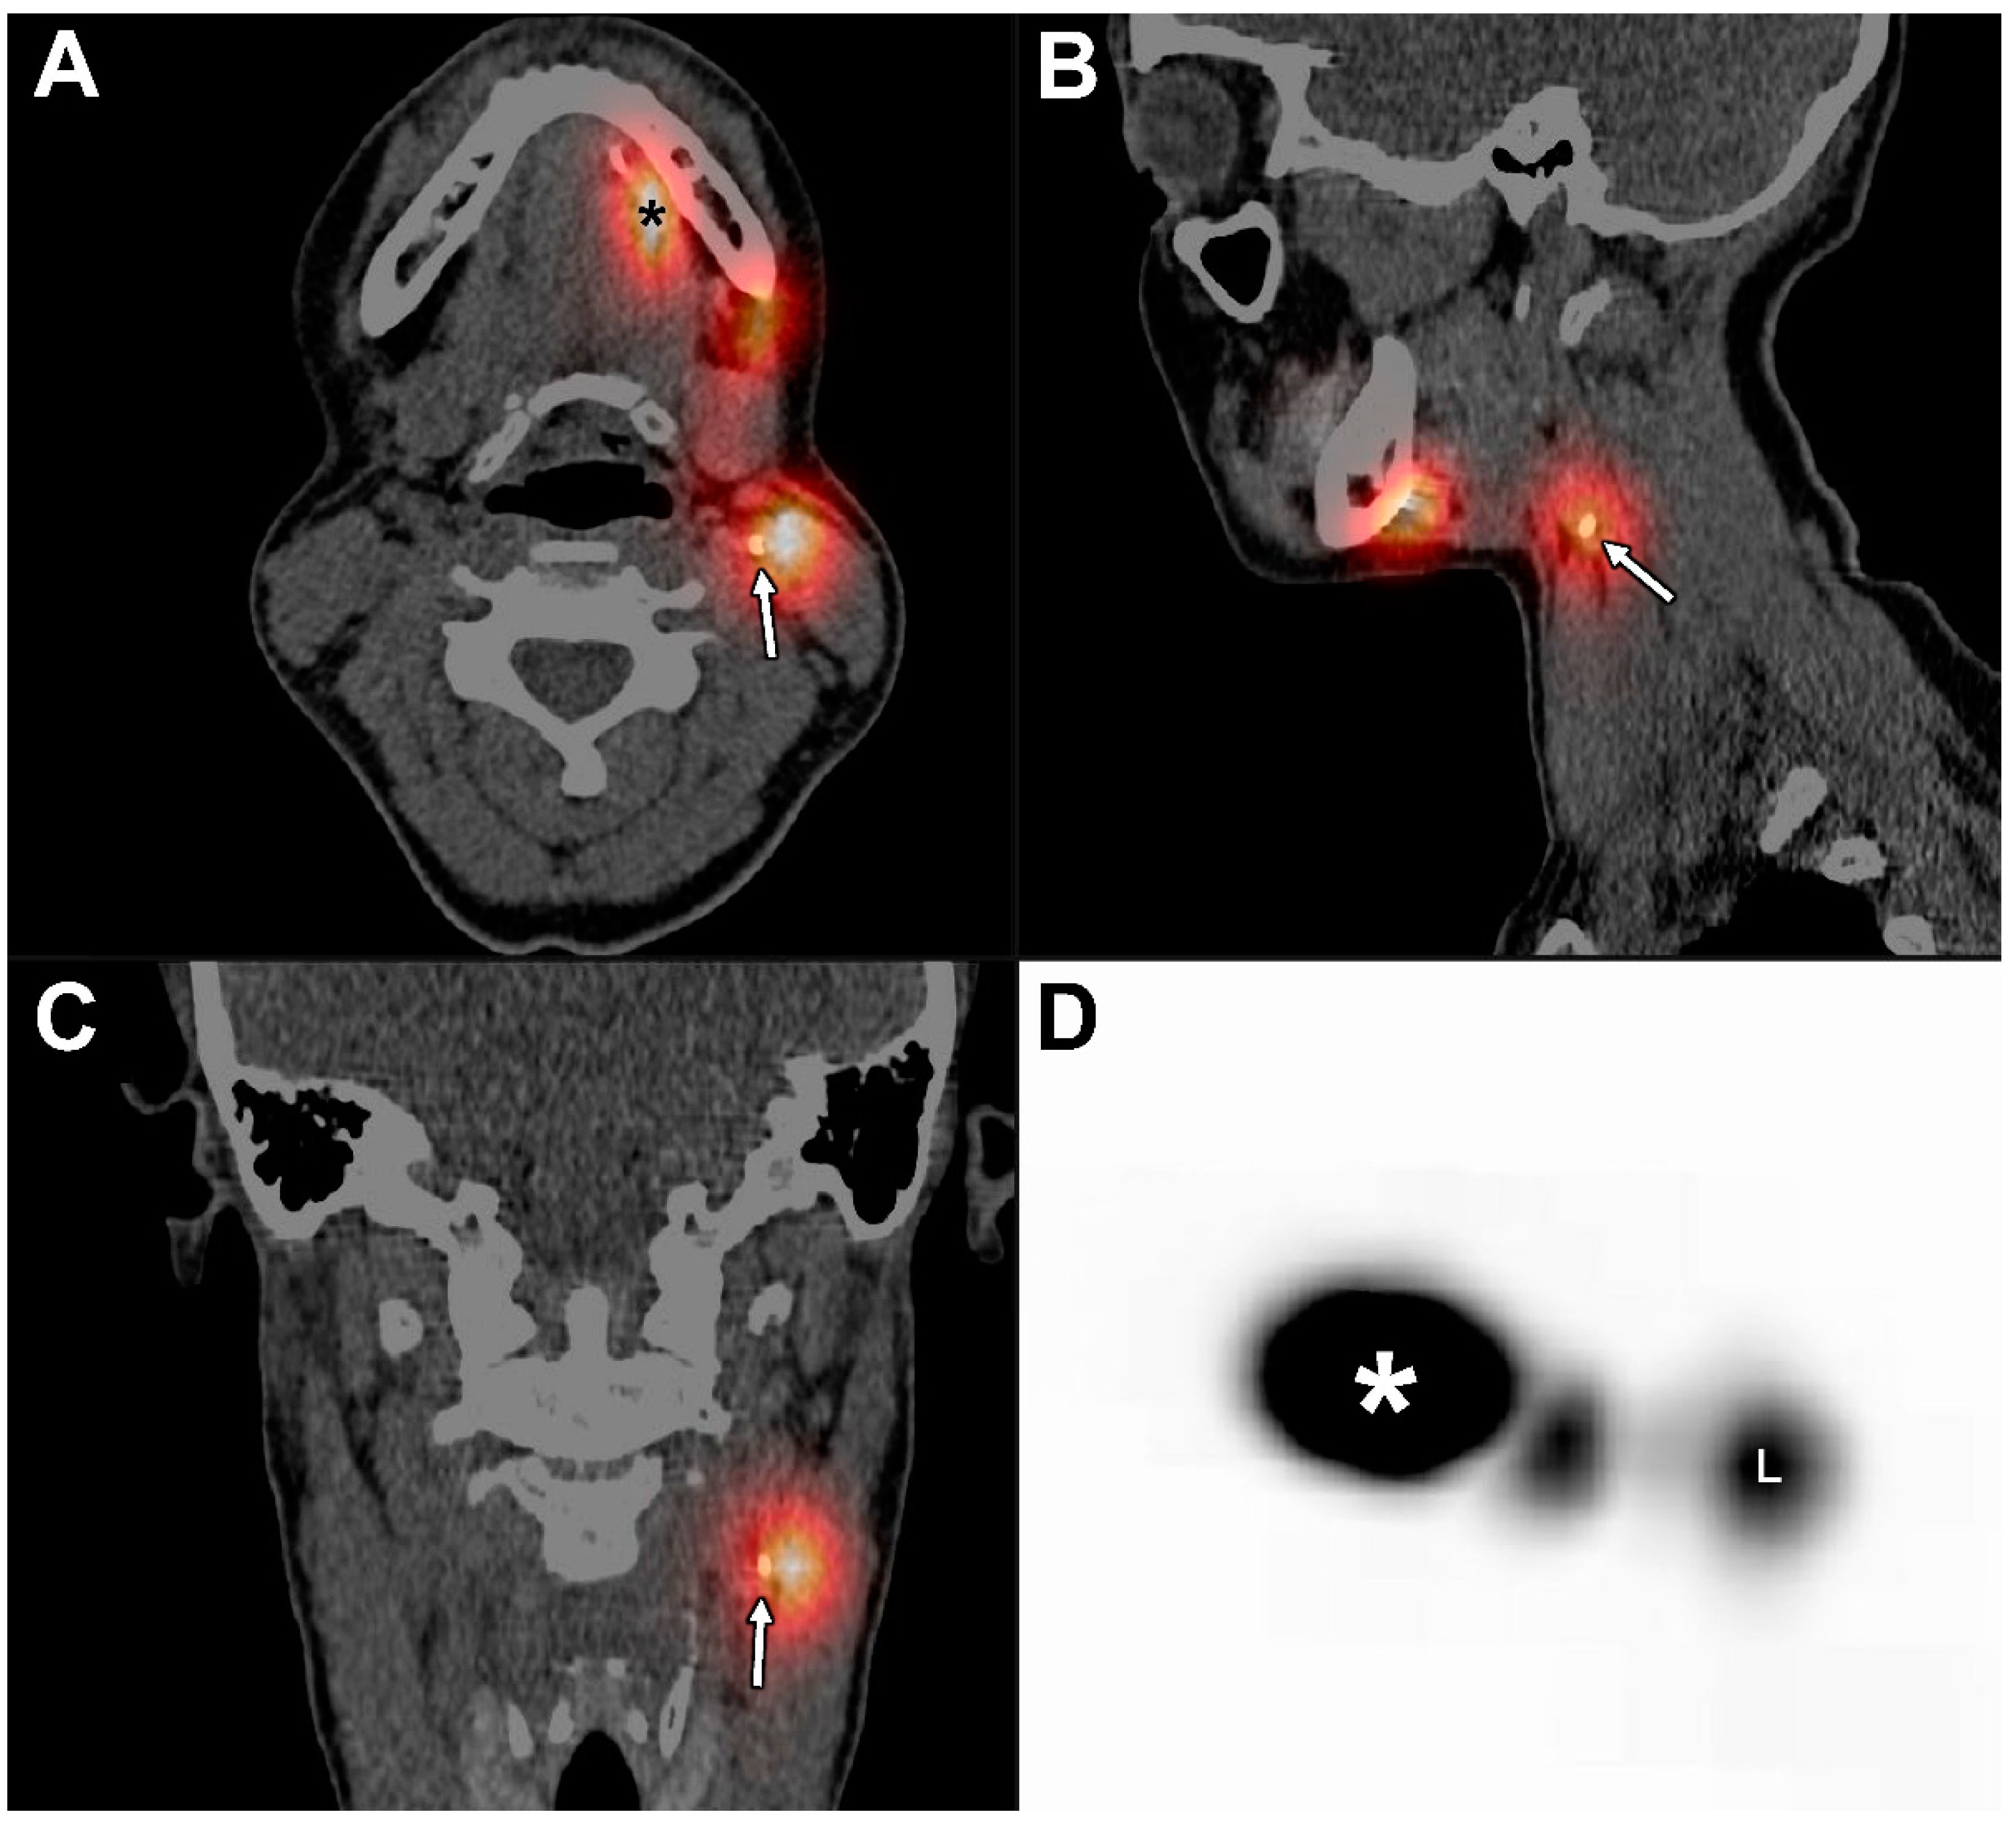

1. Introduction

2.2. Study Design

2.4. Scintigraphy and SPECT/CT

2.5. Evaluation and Analyses